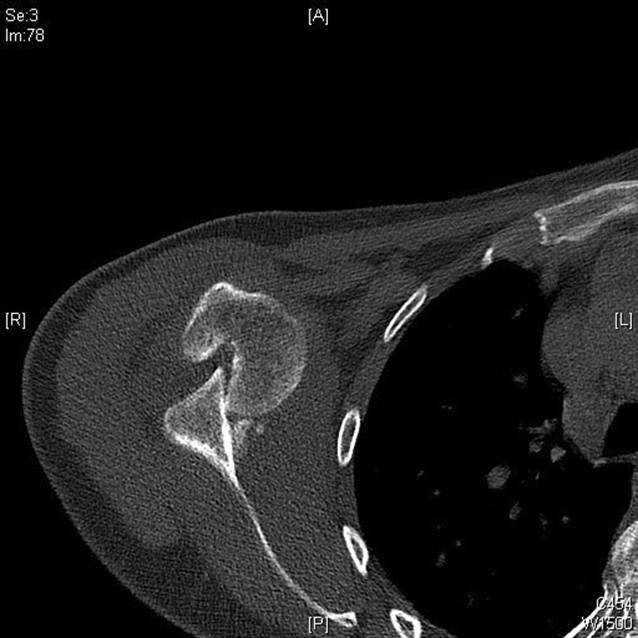

Radiologischer Befund

Auf der mitgeführten Röntgenaufnahme der Schulter in 2 Ebenen sowie der folgenden Computertomographie (CT) zeigte sich eine vordere Schulterluxation mit einem tiefgreifenden, V‑förmigen dorsalen Defekt des Humeruskopfes im Sinne einer ausgeprägten Hill-Sachs-Delle. Diese umfasste in der Tiefe etwa die Hälfte des Humeruskopfdurchmessers. Ebenso zeigte sich ein medial disloziertes, residuelles knöchernes Fragment des ventralen Glenoids im Sinne einer knöchernen Bankart-Läsion (Abb. 1).